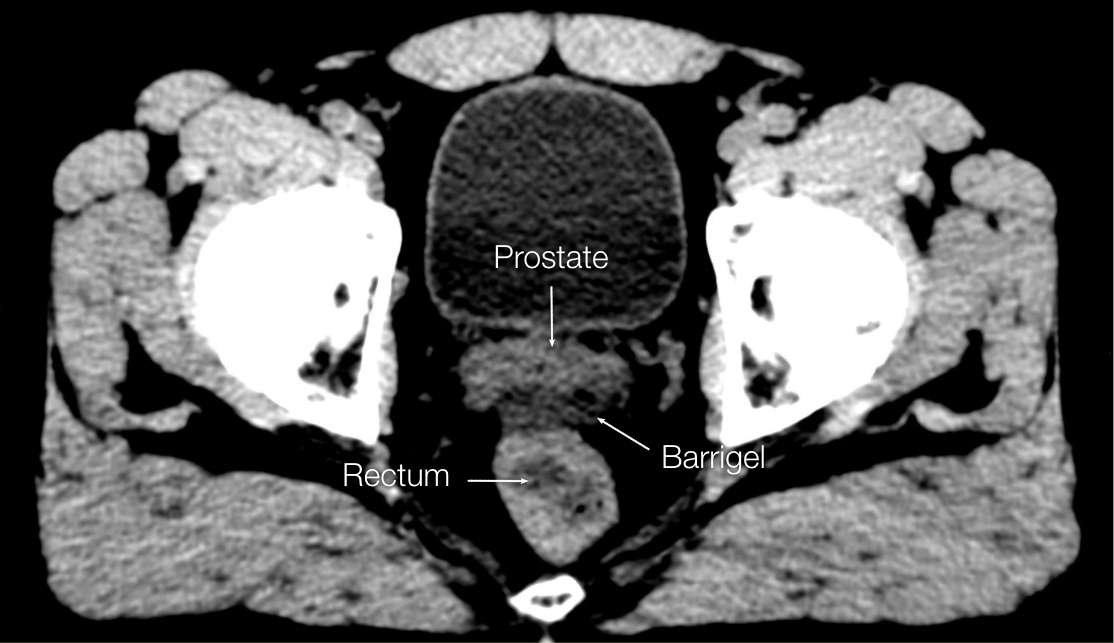

OPTIMIZING CT IMAGES

OPTIMIZING CT

IMAGES

Before (left) and after (right) adjusting window & level settings to enhance contrast and texture

CT images sourced from the Barrigel Pivotal Trial